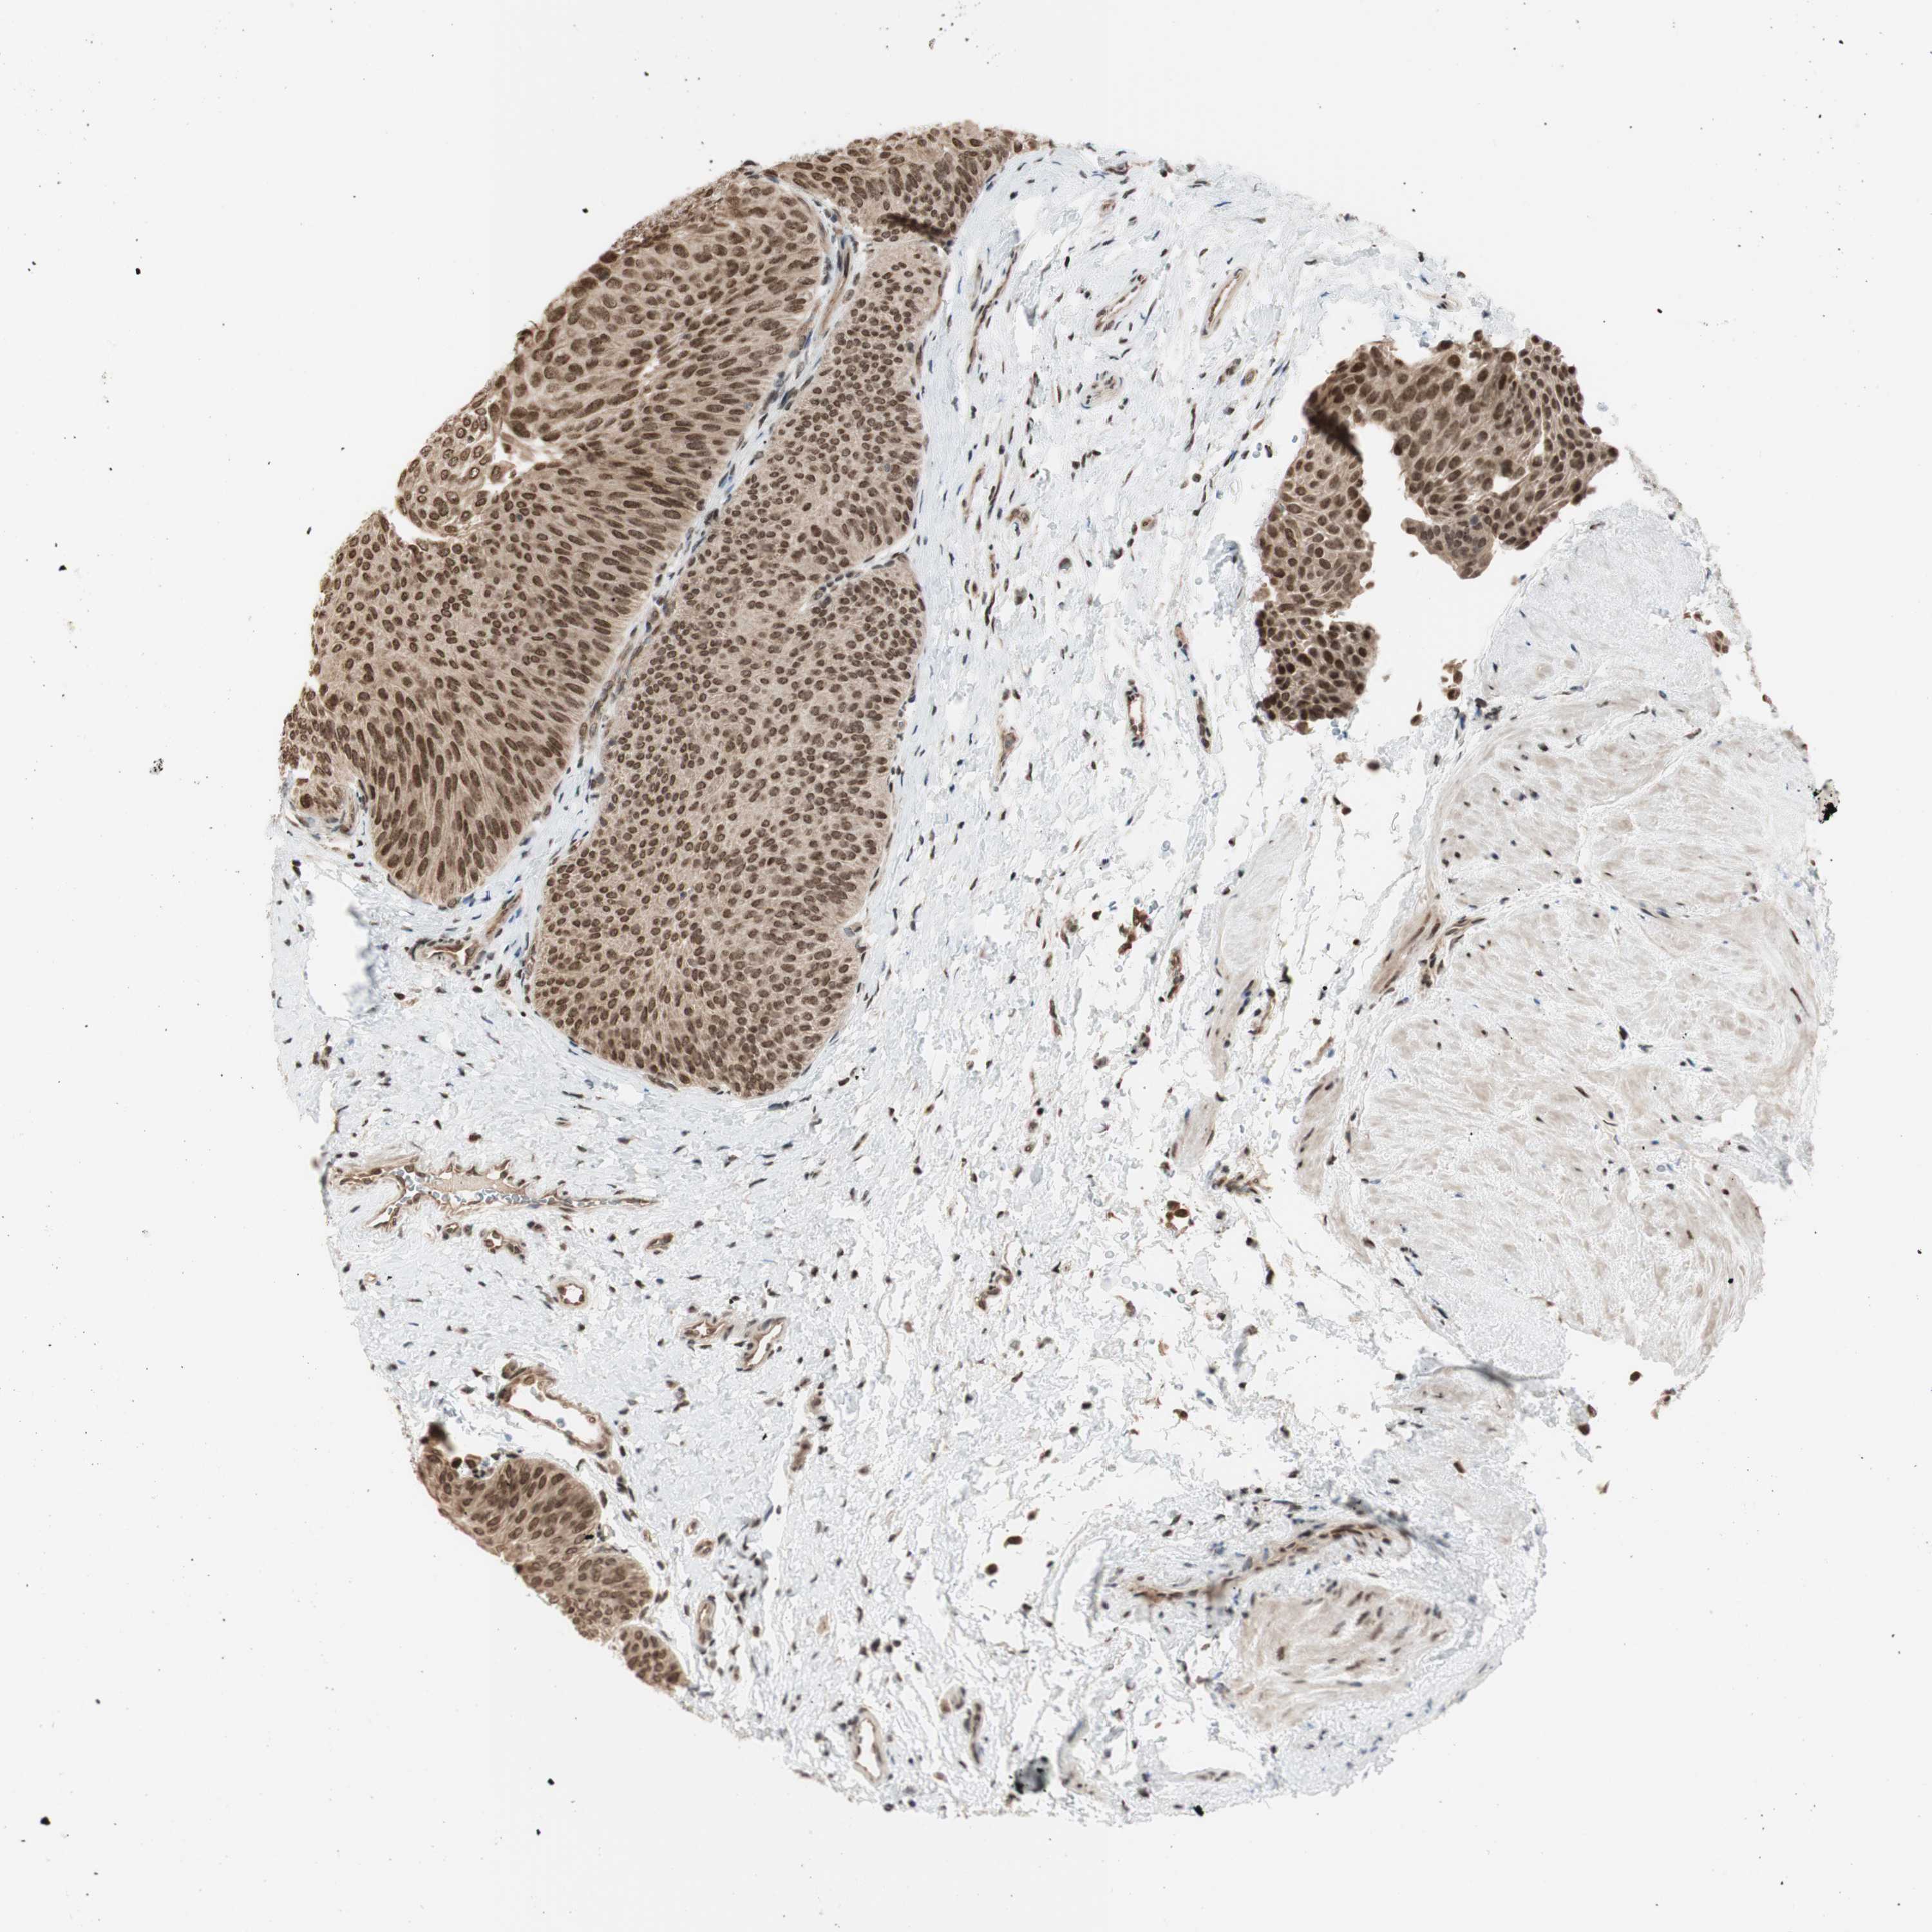

UROTHELIAL CANCER - Protein expressioni

A mouse-over function shows sample information and annotation data. Click on an image to view it in a full screen mode. Samples can be filtered based on level of antibody staining by selecting one or several of the following categories: high, medium, low and not detected. The assay and annotation is described here.

Antibody stainingi

Antibody staining in the annotated cell types in the current human tissue is reported as not detected, low, medium, or high, based on conventional immunohistochemistry profiling in selected tissues. This score is based on the combination of the staining intensity and fraction of stained cells.

Each image is clickable and will lead to virtual microscopy that enables deeper exploration of all samples and also displays staining intensity scores, fraction scores and subcellular localization as well as patient and tissue information for each sample.

Antibody HPA008700

Staining

High

Medium

Low

Not detected

Intensity

Strong

Moderate

Weak

Negative

Quantity

>75%

75%-25%

<25%

None

Location

Nuclear

Cytoplasmic/membranous

Cytoplasmic/membranous,nuclear

Urothelial carcinoma, Low grade

Urothelial carcinoma, High grade